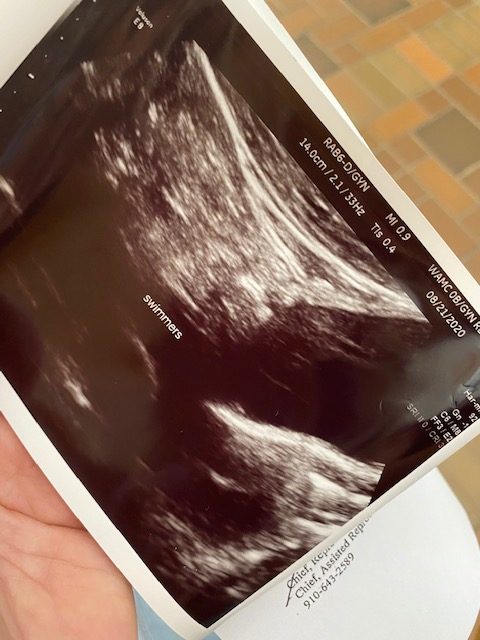

Arriving at Womack I was brought right into the ultrasound room where I handed the sperm to the nurse or physician who was performing the IUI. You undress from the waist down, lay back, relax, and they insert a catheter into your uterus while watching on the ultrasound machine so they can inject the sperm in the most ideal upper part of the uterus. They remove the catheter slowly (my clinic printed an ultrasound image of the sperm in the uterus as a souvenir, lol) and then you lay down and rest for 10 minutes or so before getting dressed and heading out. Voila, you are one step closer to making a baby, you now may go about your life and wait 2 weeks until your blood pregnancy test to see if it worked.